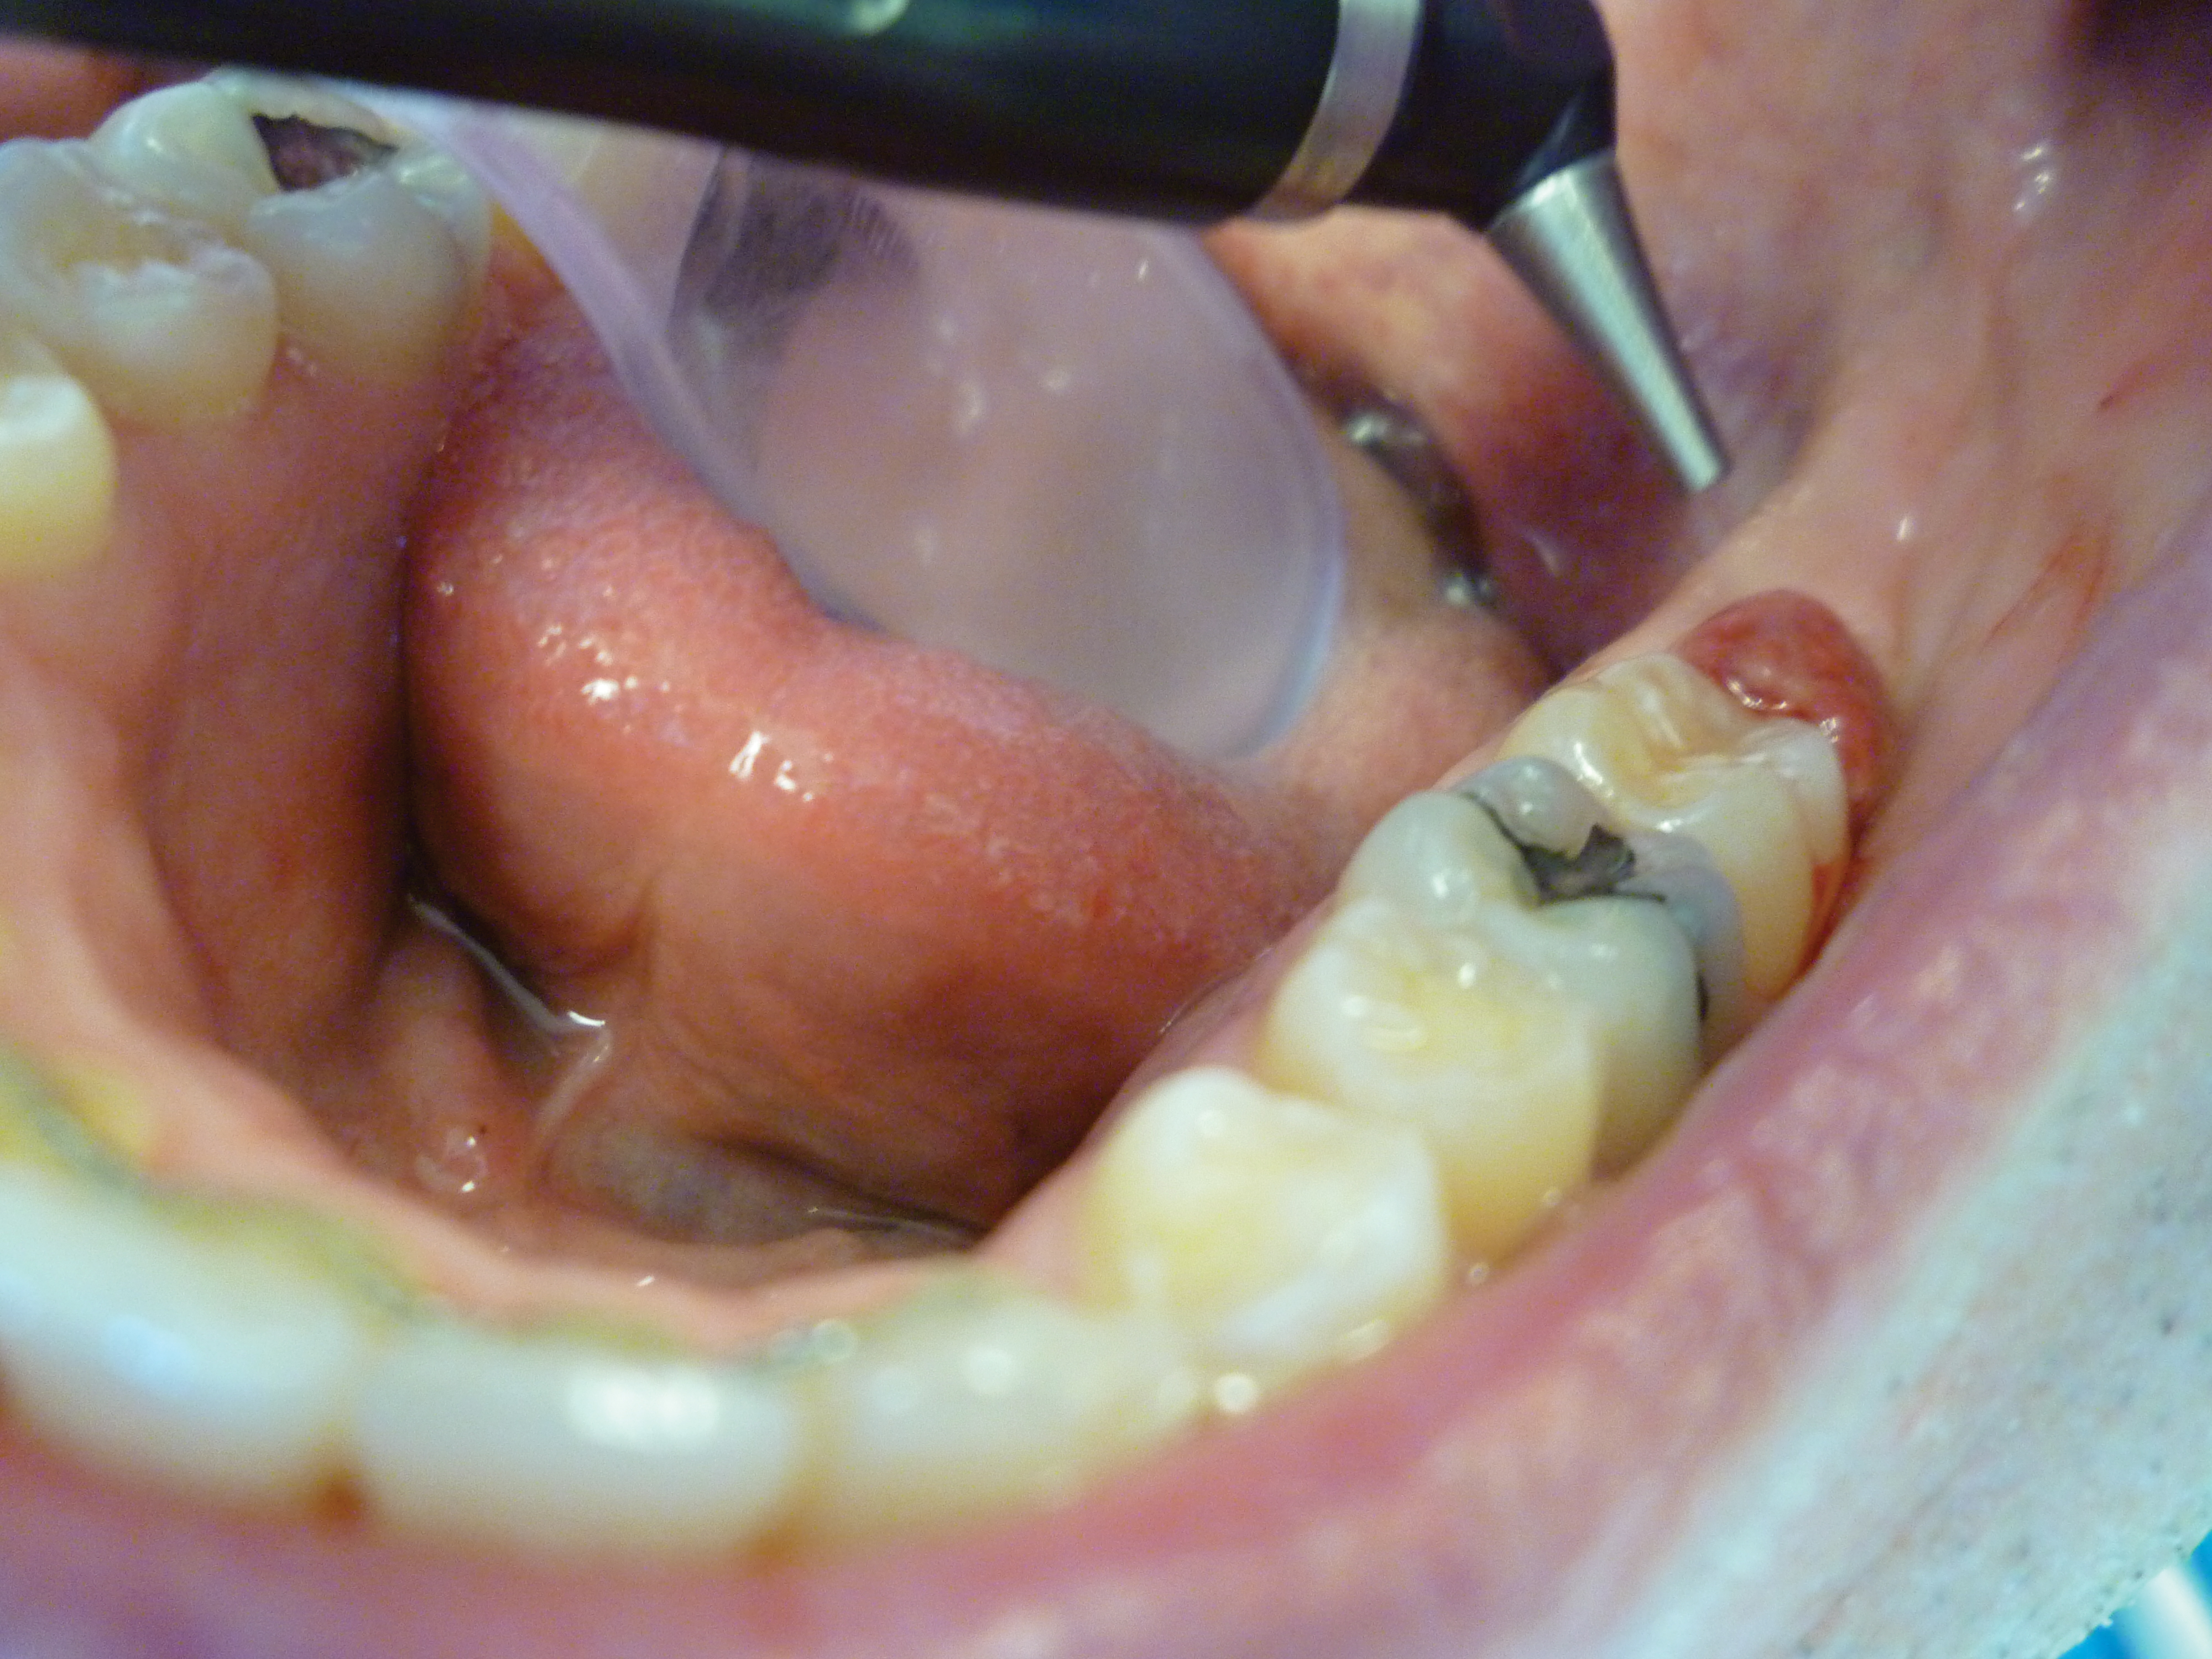

The patient presented with a raised, inflamed, painful operculum distal to the left mandibular second molar (Figure 3). The lesion was red, edematous, and bled easily. A periodontal pocket on the distal of the second molar was >6 mm deep. There was no evidence of abscess.

Fig 3. Preoperative view of the inflamed operculum.

Figure 3

Fig 5. The ablation of the inflamed tissue began.

Figure 5